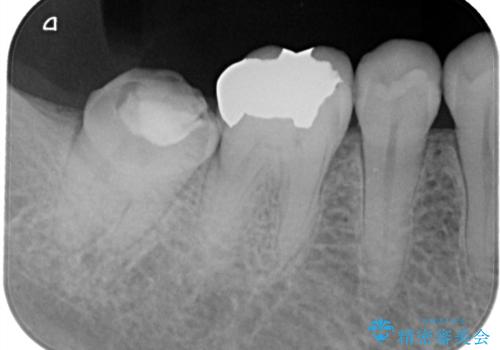

レントゲン写真から古い詰め物が神経と近接している事がわかります。万一に備え、ラバーダムシートを装着しながら治療を行いました。(万が一、虫歯の除去中に神経が露出した場合、神経を唾液から守るため。)